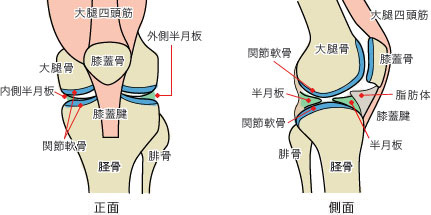

膝の構造について

正常な膝関節の構造図

関節軟骨

関節軟骨は骨と骨が擦れあう時に生じる摩擦を非常に少なくします。また、骨にかかる衝撃を和らげるクッションのような働きもしています。

関節を曲げるときには、関節軟骨に圧力が加わり、関節軟骨から関節液が押し出され、曲げ伸ばしがスムーズになるという仕組みにもなっています。

半月板

半月板は、内側半月板と外側半月板があり、関節の適合性を良くし安定性を与えながら、大腿部から受ける体重の荷重を分散し衝撃を吸収するクッションの働きをしています。

関節液

関節液は透明で粘り気がある液体で、ヒアルロン酸やたんぱく質を含んでいます。このヒアルロン酸とたんぱく質の複合体が関節軟骨の表面を覆って、関節がスムーズに動くように潤滑液の働きをしているのです。「関節液」=「潤滑油」のようなものです。また、滑膜で作られた関節液は関節軟骨に栄養を与える働きもあります。